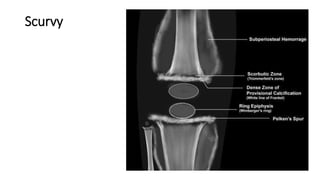

Scurvy